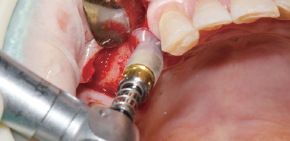

A Clinical Case using Ø3.5/4.0 Harvesting Drill

by Dr. Soohong Kim, DDS, Ph.D

-

Drilling at 300 rpm with irrigation was carried out after marking implant and harvesting position.

The Silicone Shield was brought into close contact with various types of bone level and prevented bone chip loss.

The amount of bone taken was easily ascertained, through the transparent Silicone Shield.

The bone was transferred to bone dish after disassembling the Silicone Shield and Stopper.

The amount of the bone was much more than expected.

After the implant placement, healing abutments were connected and carried out GBR in the defected area.

* 2 Step Harvesting : Drilling to 7mm is recommended after transferring bone chips to bowl since the Stopper & Silicone Shield are fully filled with bone chips while 4mm drilling.